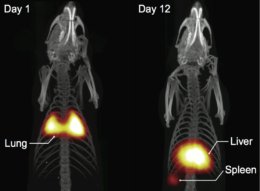

New imaging tech makes clearer images than MRIs http://bit.ly/1OLr3q0

#healthpic.twitter.com/E9Hvt1ZZzy 09:03 ಪೂರ್ವಾಹ್ನ - ಮೇ 26,2016 · ವಿವರಗಳು6 ಮರುಟ್ವೀಟಿಸುವಿಕೆಗಳು 9ಇಷ್ಟಗಳು

How can copper help fight

#cancer,#obesity & more http://bit.ly/1OLpRmq pic.twitter.com/goN3aeUv1B 10:03 ಪೂರ್ವಾಹ್ನ - ಮೇ 25,2016 · ವಿವರಗಳು5 ಮರುಟ್ವೀಟಿಸುವಿಕೆಗಳು 15ಇಷ್ಟಗಳು